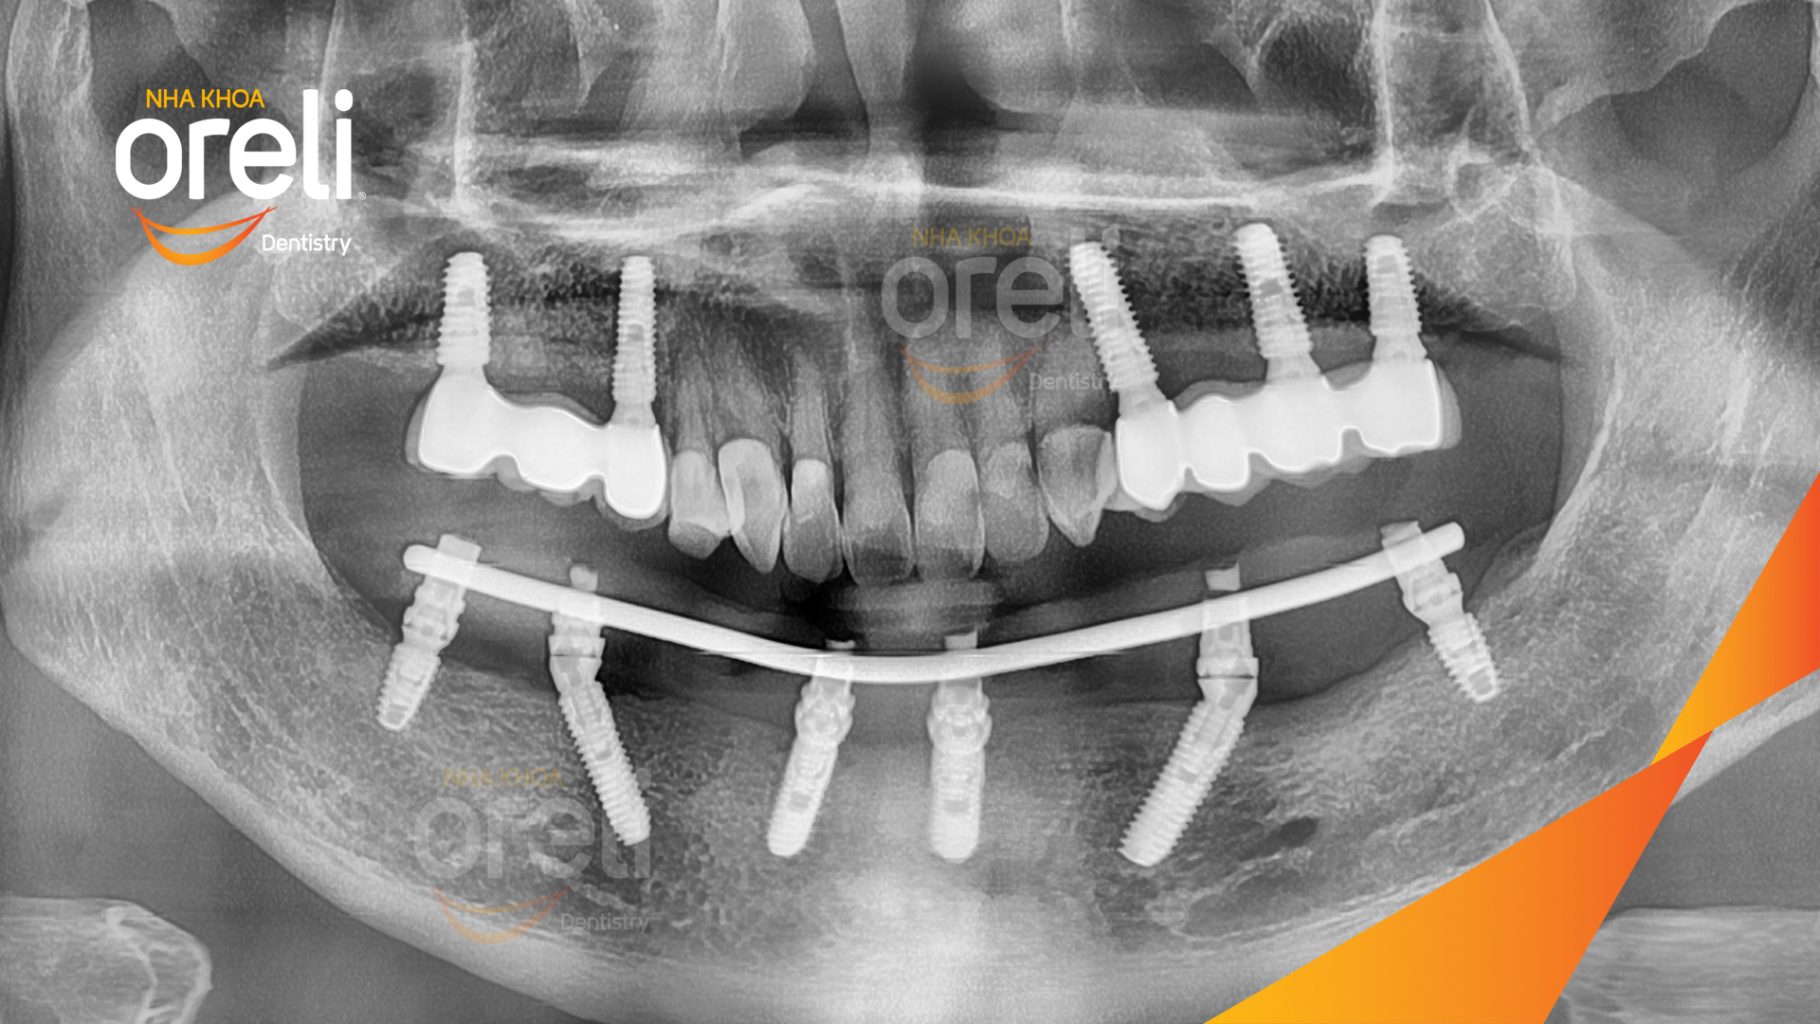

Tình trạng: Mất răng nhai vùng hàm trên và dưới

Giải pháp: Trồng răng implant toàn hàm dưới và vùng răng sau hàm trên

Thời gian: 3 tháng

Kết quả: Ăn nhai tốt và thoải mái trong miệng

Hình ảnh thực tế